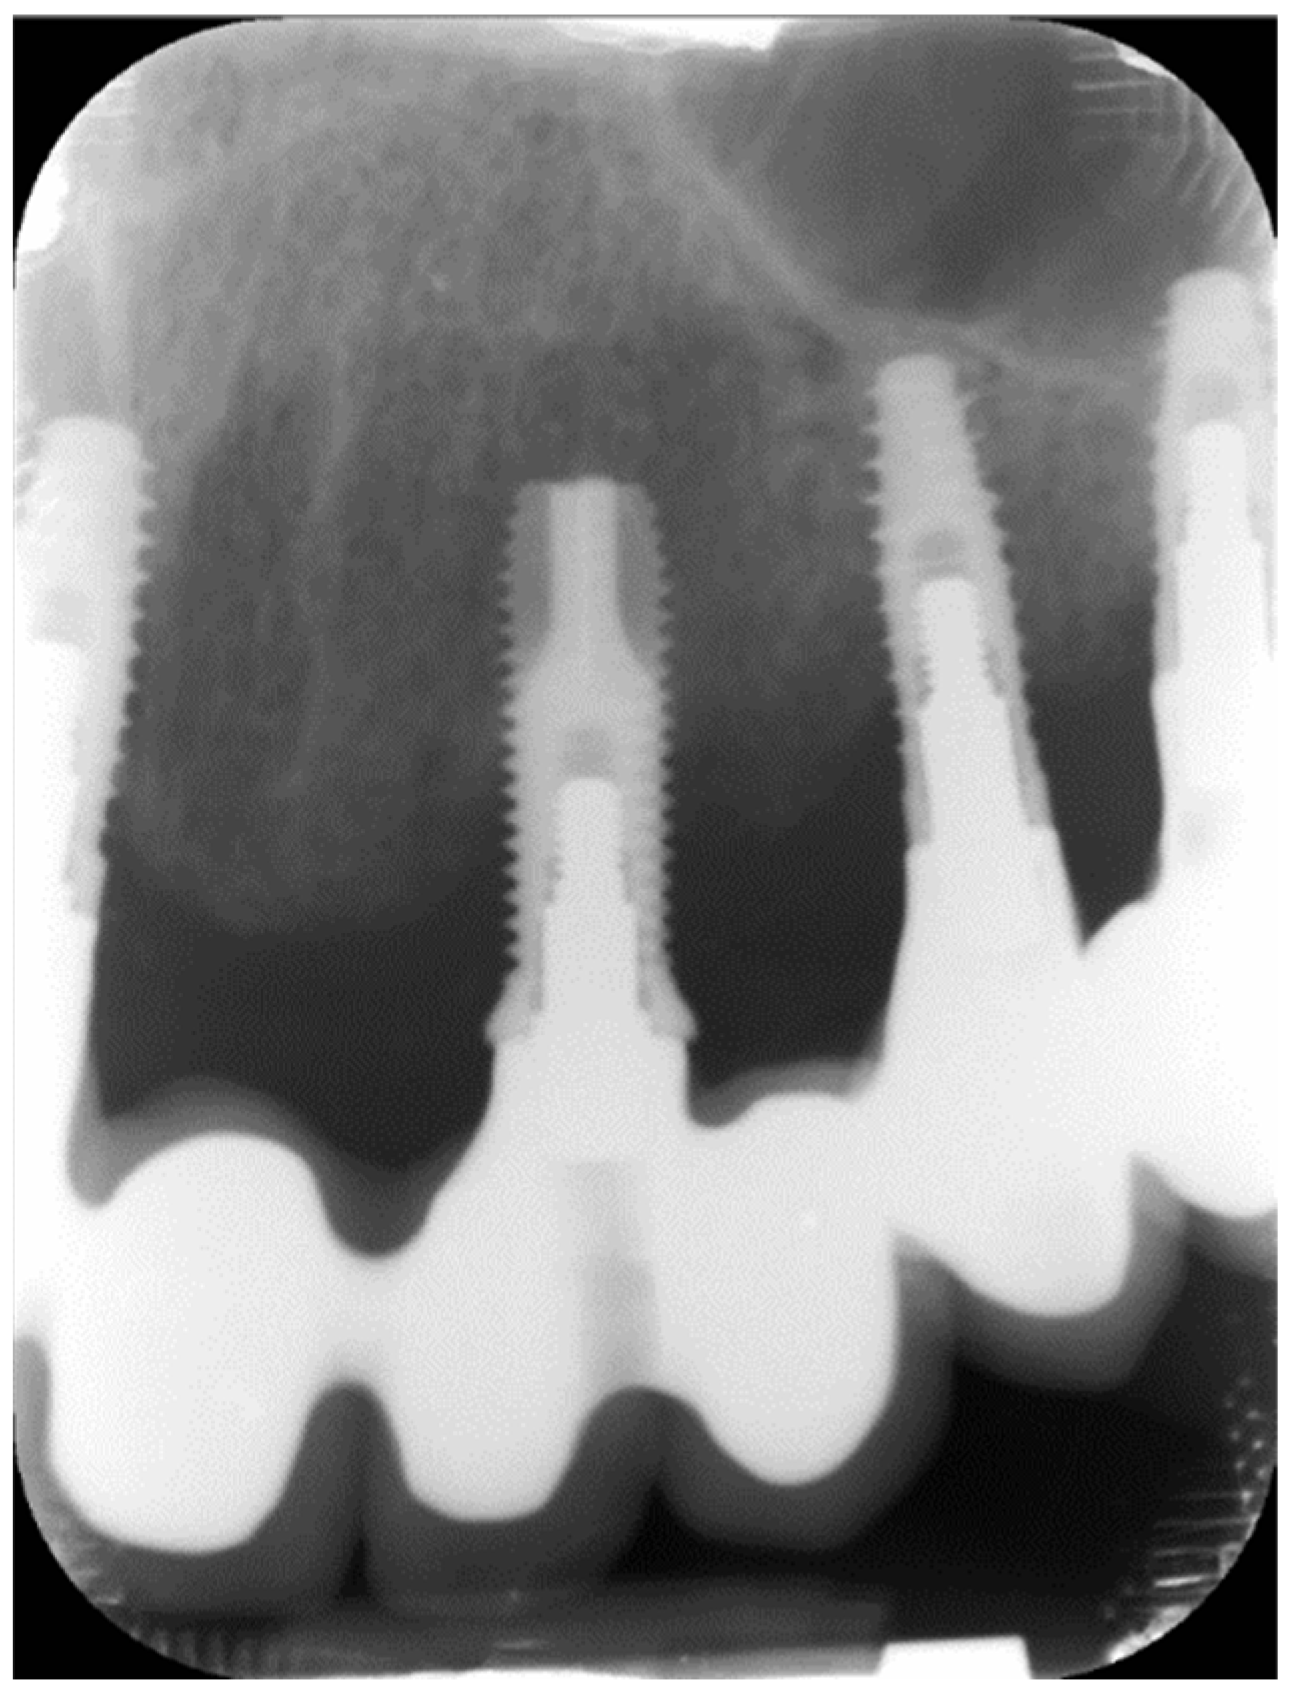

:1. Introduction

2. Method and Materials

2.2. Setting and Participants

| BL (mm) | 0.5 ± 0.6 | 3.8 ± 2.1 | 1.35 | 1.22–1.44 | <0.001 |